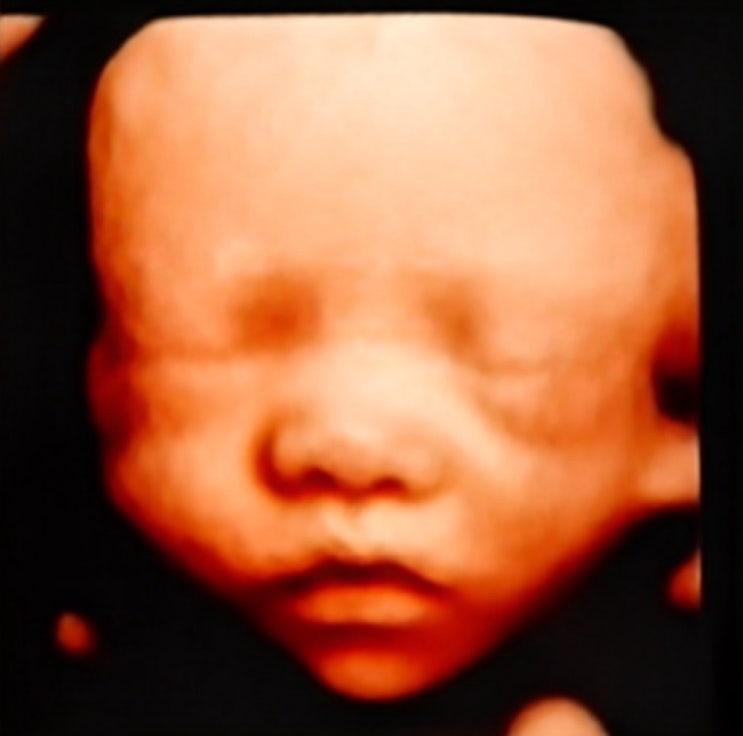

[임신30주차] 입체초음파 / 액상철분제처방 / 압박스타킹, 손목보호대 처방 / 먹고싶은거 다먹는 임산부일상

초기에는 시간이 잘안가더니 임신 후기되니까 그냥 시간이 미쳐따ㅠㅠ 너무빨리간다.. 30주부터 진짜 나 임...